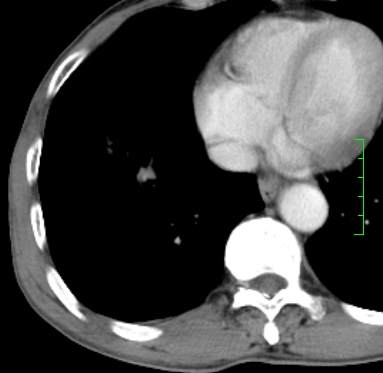

m,73y。膝关节疼痛伴双下肢水肿。入院常规胸片发现结节灶。增强为静脉期。

指套征,强化明显,近侧肺组织局限性肺气肿,考虑支气管类癌,慢支、肺气肿、双上陈旧性tb、冠脉钙化。

鉴别:先天性支气管闭锁,变态反应性支气管肺曲霉菌病,肺癌,支气管囊肿,支扩黏液嵌塞。

1)考虑右肺下叶周围型肺癌。2)右肺上叶及左肺感染性病变(结核可能)。3)肺气肿。4)冠状动脉钙化。